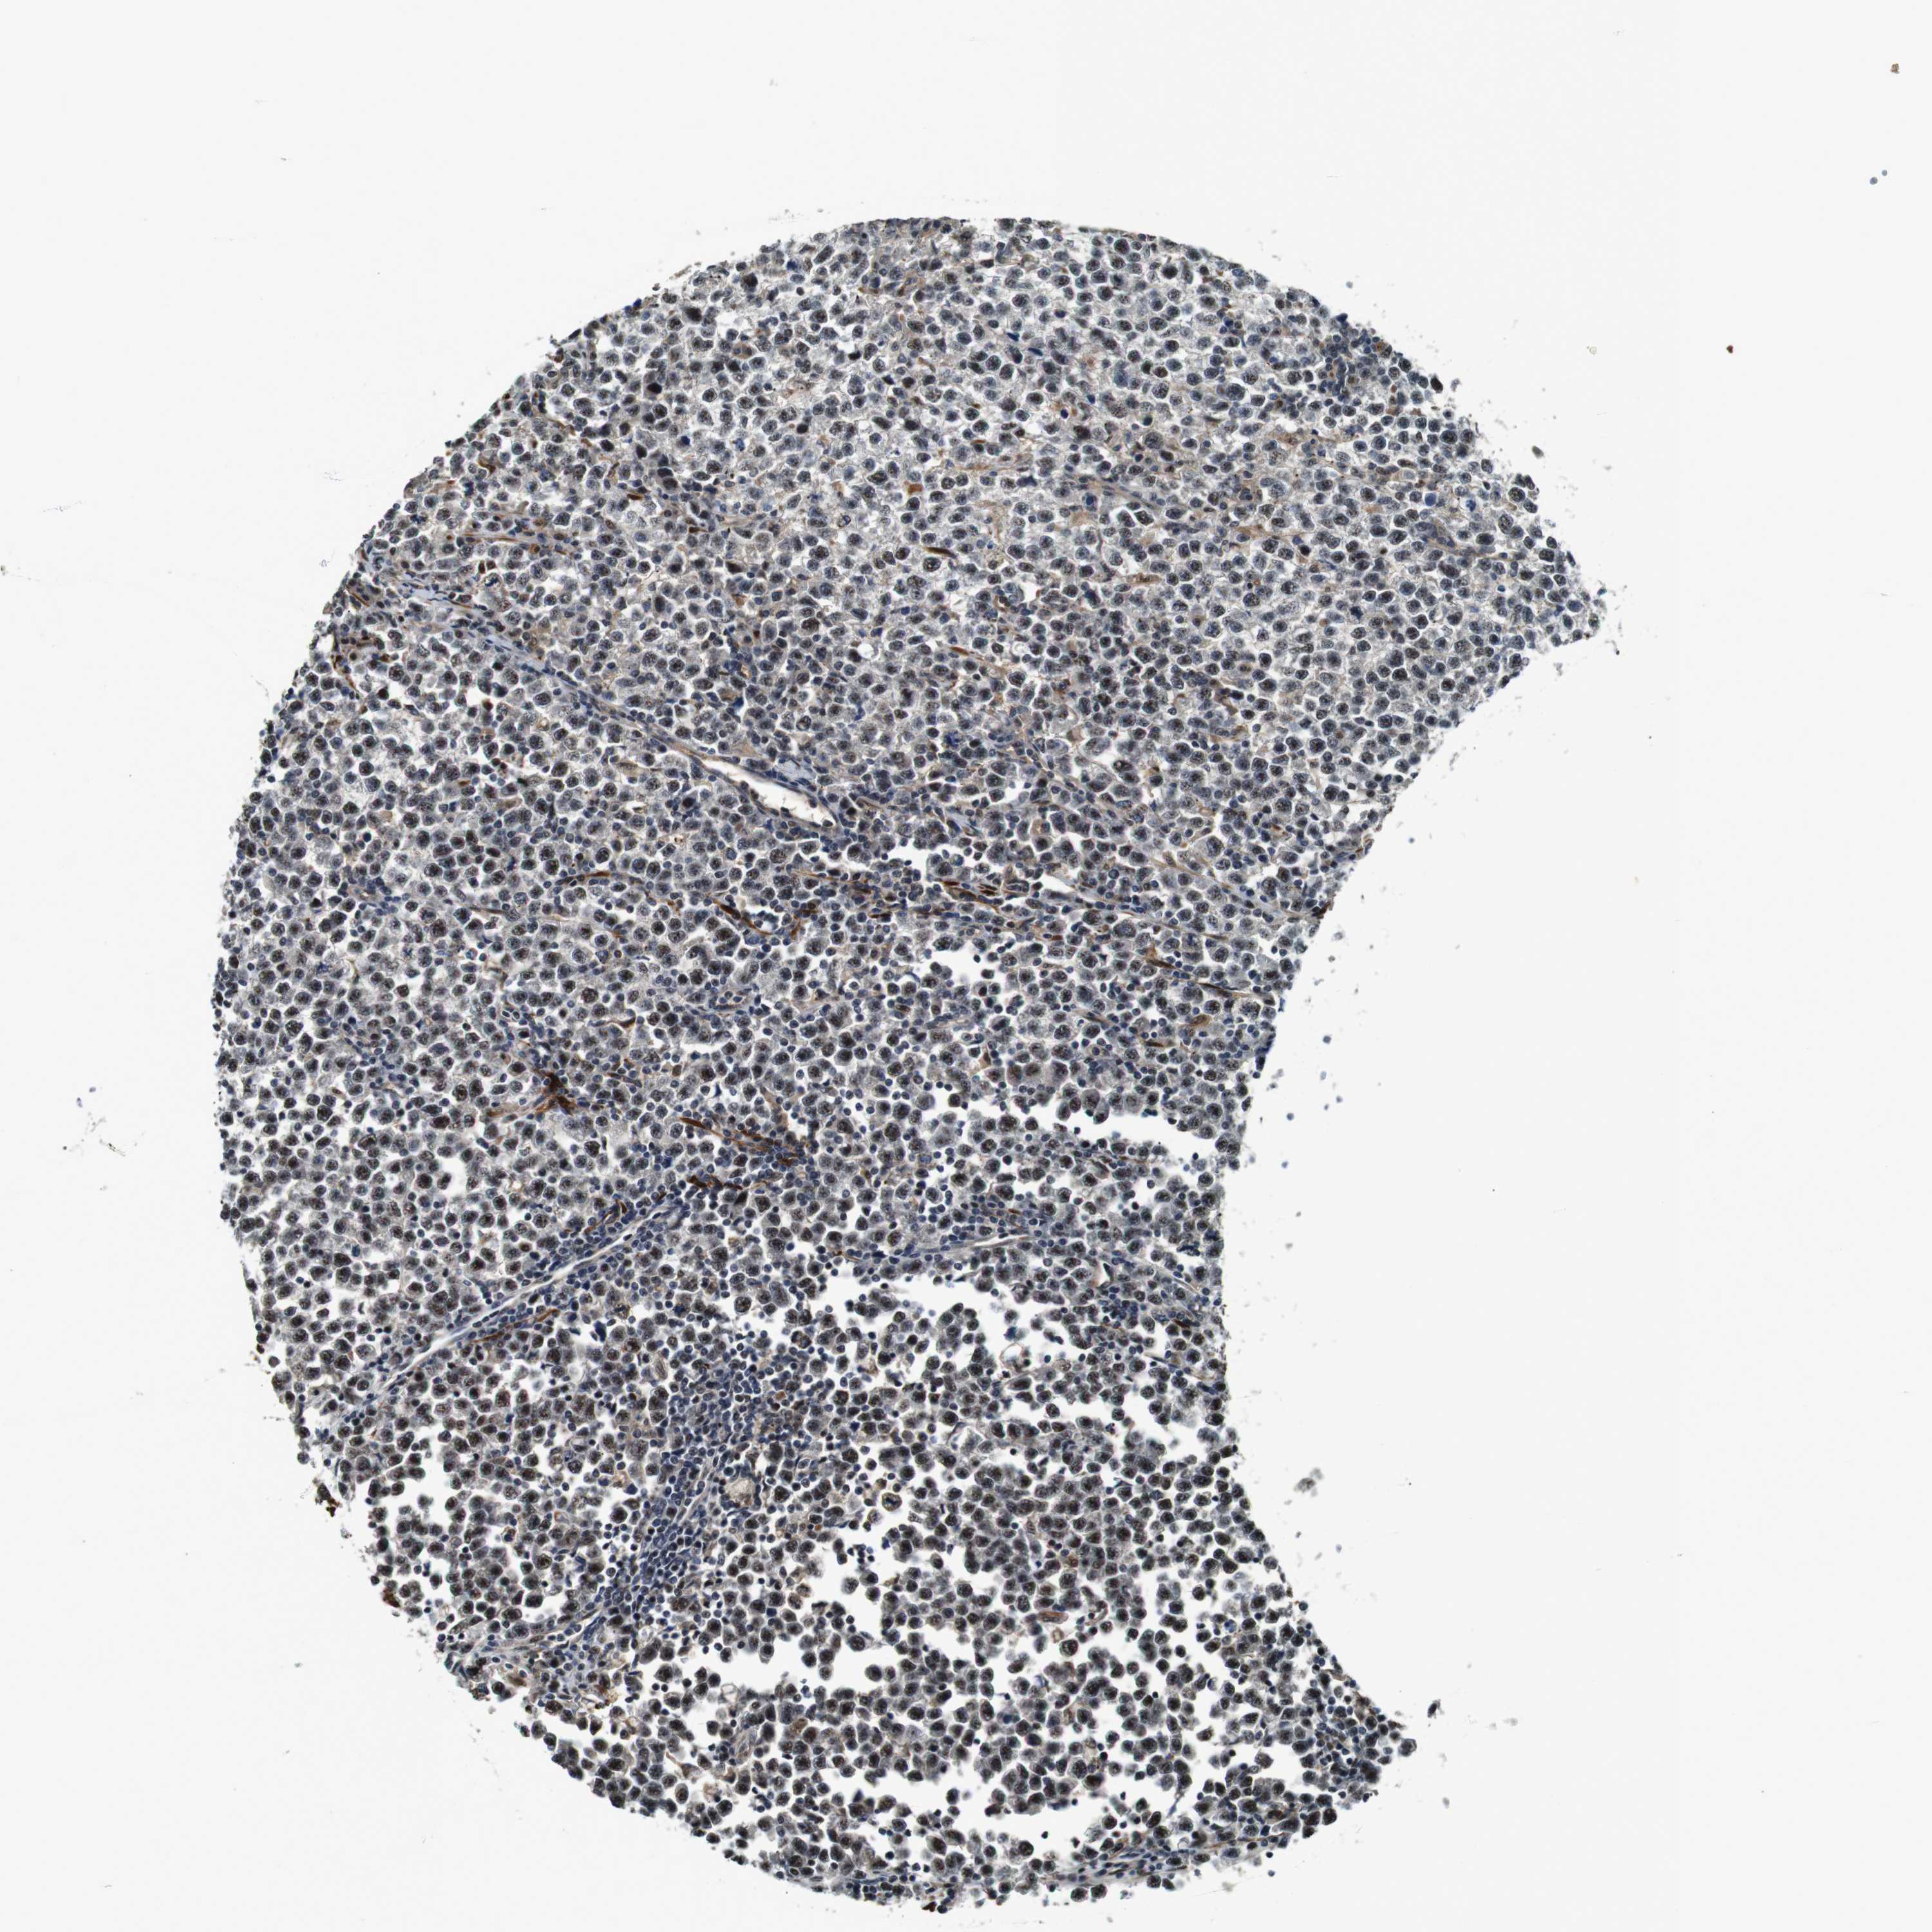

TESTIS CANCER - Protein expressioni

A mouse-over function shows sample information and annotation data. Click on an image to view it in a full screen mode. Samples can be filtered based on level of antibody staining by selecting one or several of the following categories: high, medium, low and not detected. The assay and annotation is described here.

Antibody stainingi

Antibody staining in the annotated cell types in the current human tissue is reported as not detected, low, medium, or high, based on conventional immunohistochemistry profiling in selected tissues. This score is based on the combination of the staining intensity and fraction of stained cells.

Each image is clickable and will lead to virtual microscopy that enables deeper exploration of all samples and also displays staining intensity scores, fraction scores and subcellular localization as well as patient and tissue information for each sample.

Antibody HPA014179

Carcinoma, Embryonal, NOS

Seminoma, NOS